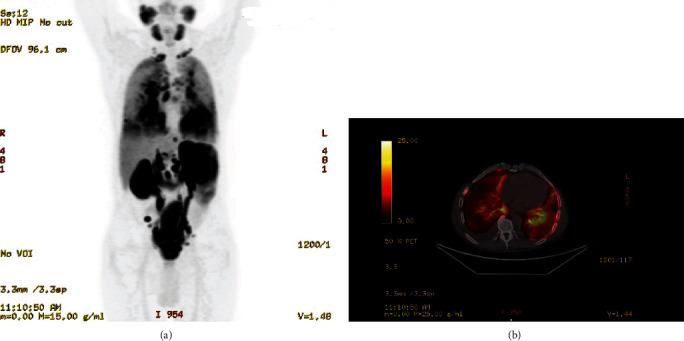

Background: Lymphangitic carcinomatosis (LC), a hallmark of advanced metastatic cancer with a poor prognosis, primarily impacts the lymphatic system of the lungs, manifesting as progressive breathlessness, cough, or hemoptysis. While prostate cancer commonly metastasizes to bones and regional lymph nodes, lung involvement is rare. This case features a patient in generally good health who presented with an insidious dry cough, leading to a diagnosis of Stage 4 prostatic adenocarcinoma with rare lymphangitic spread to the lungs. Case Presentation: A 70-year-old male in good health presented with chest tightness, a dry cough, and sudden left testicular swelling. Imaging revealed interstitial lung markings, severe left hydronephrosis, and prostatomegaly. A prostate biopsy confirmed adenocarcinoma. A PET-CT scan raised significant concern for LC, prompting the initiation of urgent inpatient chemotherapy with docetaxel. Conclusion: LC is a metastatic pattern commonly associated with solid tumors, particularly breast, gastric, and lung cancers. Its occurrence in prostate cancer is exceptionally rare. This condition is typically linked with advanced disease and a poor prognosis, often serving as a critical indicator of an underlying malignancy that may otherwise go undetected.

背景:淋巴管癌肿(LC)是预后不良的晚期转移性癌症的标志,主要影响肺部淋巴系统,表现为进行性呼吸困难、咳嗽或咯血。虽然前列腺癌通常会转移到骨骼和区域淋巴结,但肺部受累的情况并不多见。本病例中的患者总体健康状况良好,但出现隐匿性干咳,最终被诊断为前列腺腺癌 4 期,并伴有罕见的肺部淋巴管转移。病例介绍:一名 70 岁男性,健康状况良好,因胸闷、干咳和突发性左侧睾丸肿胀就诊。影像学检查发现肺间质性病变、严重的左肾积水和前列腺肿大。前列腺活检证实为腺癌。PET-CT 扫描显示该患者患有 LC,这促使他接受了多西他赛住院化疗。结论LC 是实体瘤(尤其是乳腺癌、胃癌和肺癌)常见的转移模式。在前列腺癌中出现这种情况极为罕见。这种情况通常与晚期疾病和不良预后有关,通常是潜在恶性肿瘤的一个重要指标,否则可能无法发现。